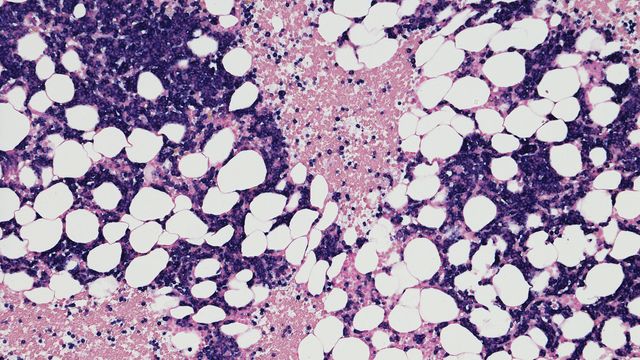

Cancerous tissue

Poster

Retrieve More Information From Limited DNA

This poster highlights how this technology can provide accurate detection of genetic variants and variant-associated methylation in colorectal cancer samples.